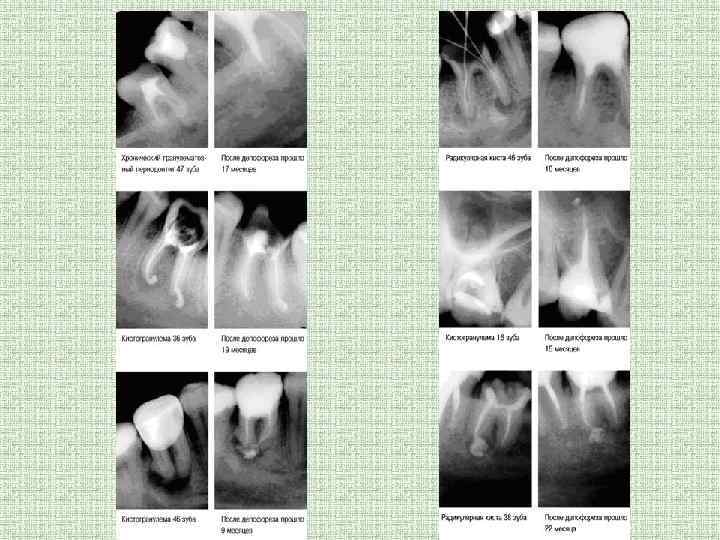

Какие заболевания можно лечить с помощью депофореза? • Данная технология позволяет вылечивать инфекционные процессы в корневых каналах в том числе, искривленных корней моляров, проблемных «восьмых» зубов, облитерованных корневых каналов зубов, покрытых коронками; пульпиты; остеолизы; периодонтиты, кистогранулемы и кисты

Результаты лечения • После обработки гидроокисью медикальция методом депофореза корень зуба становится стерильной системой, полностью закрытой от инвазии микроорганизмов. Он стабилен, может выполнять все свои функции.